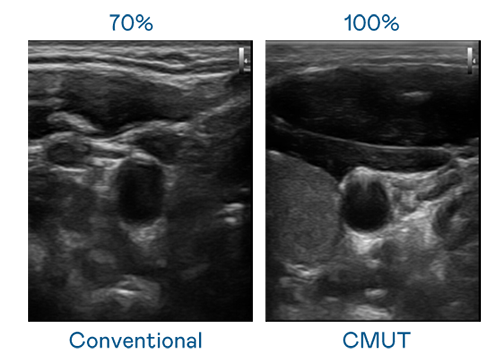

CMUT 技术是一种用电容式微机电元件来产生超音波讯号的技术。与传统 PZT 压电式技术相比,CMUT 频宽增加 30%,更宽频的超音波讯号让影像解析度大幅提升,是实现高影像品质医疗超音波扫描、促进精准医疗发展的关键技术。

大频宽带来超清晰影像

超音波影像的解析度高低,首先取决于探头能发出的讯号频宽。713贵宾会 CMUT 可提供高清晰的超音波讯号,提供高频宽、高灵敏度、影像纹理细节更高的超音波影像,协助医护人员缩短影像判读时间及利用精准的医疗影像进行诊断。